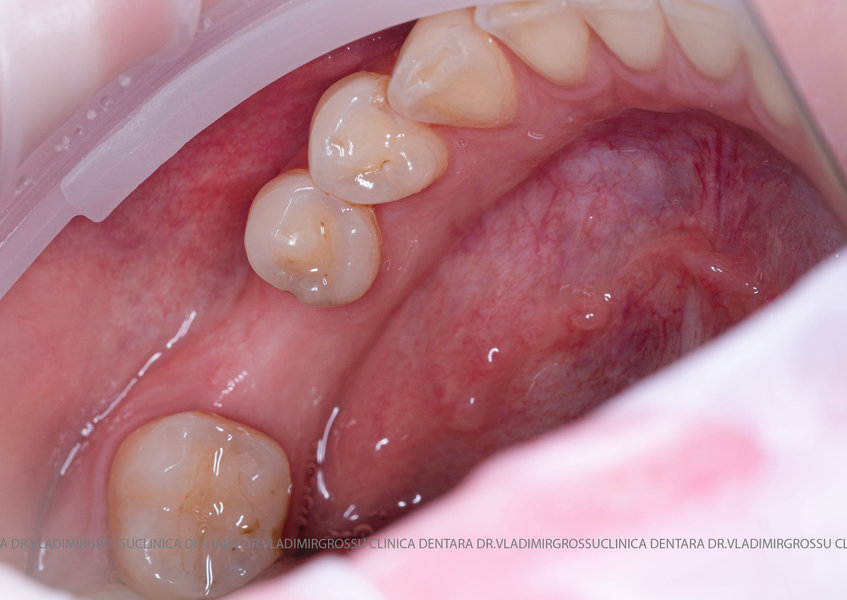

Aditia gingivală este o procedură chirurgicală ce corectează diverse probleme estetice și funcționale, cum ar fi recesiunea gingivală. În implantologia modernă, aditia de țesut moale este utilizată aproape în fiecare intervenție de inserție a implantului dentar pentru a asigura un aspect estetic natural și o bună integrare a implantului în cavitatea bucală.

Adiția osoasă are un rol crucial pentru poziționarea corectă și stabilă a implanturilor dentare. Clinica stomatologică Dr. Grossu din Chișinău promovează o abordare chirurgicală estetică și predictibilă, adaptată fiecărui caz în parte.

Medicii noștri au o vastă experiență atât în chirurgia estetică, cât și în protezarea cu un grad înalt de naturalitate, ceea ce ne permite să gestionăm cu succes și cele mai complexe cazuri.